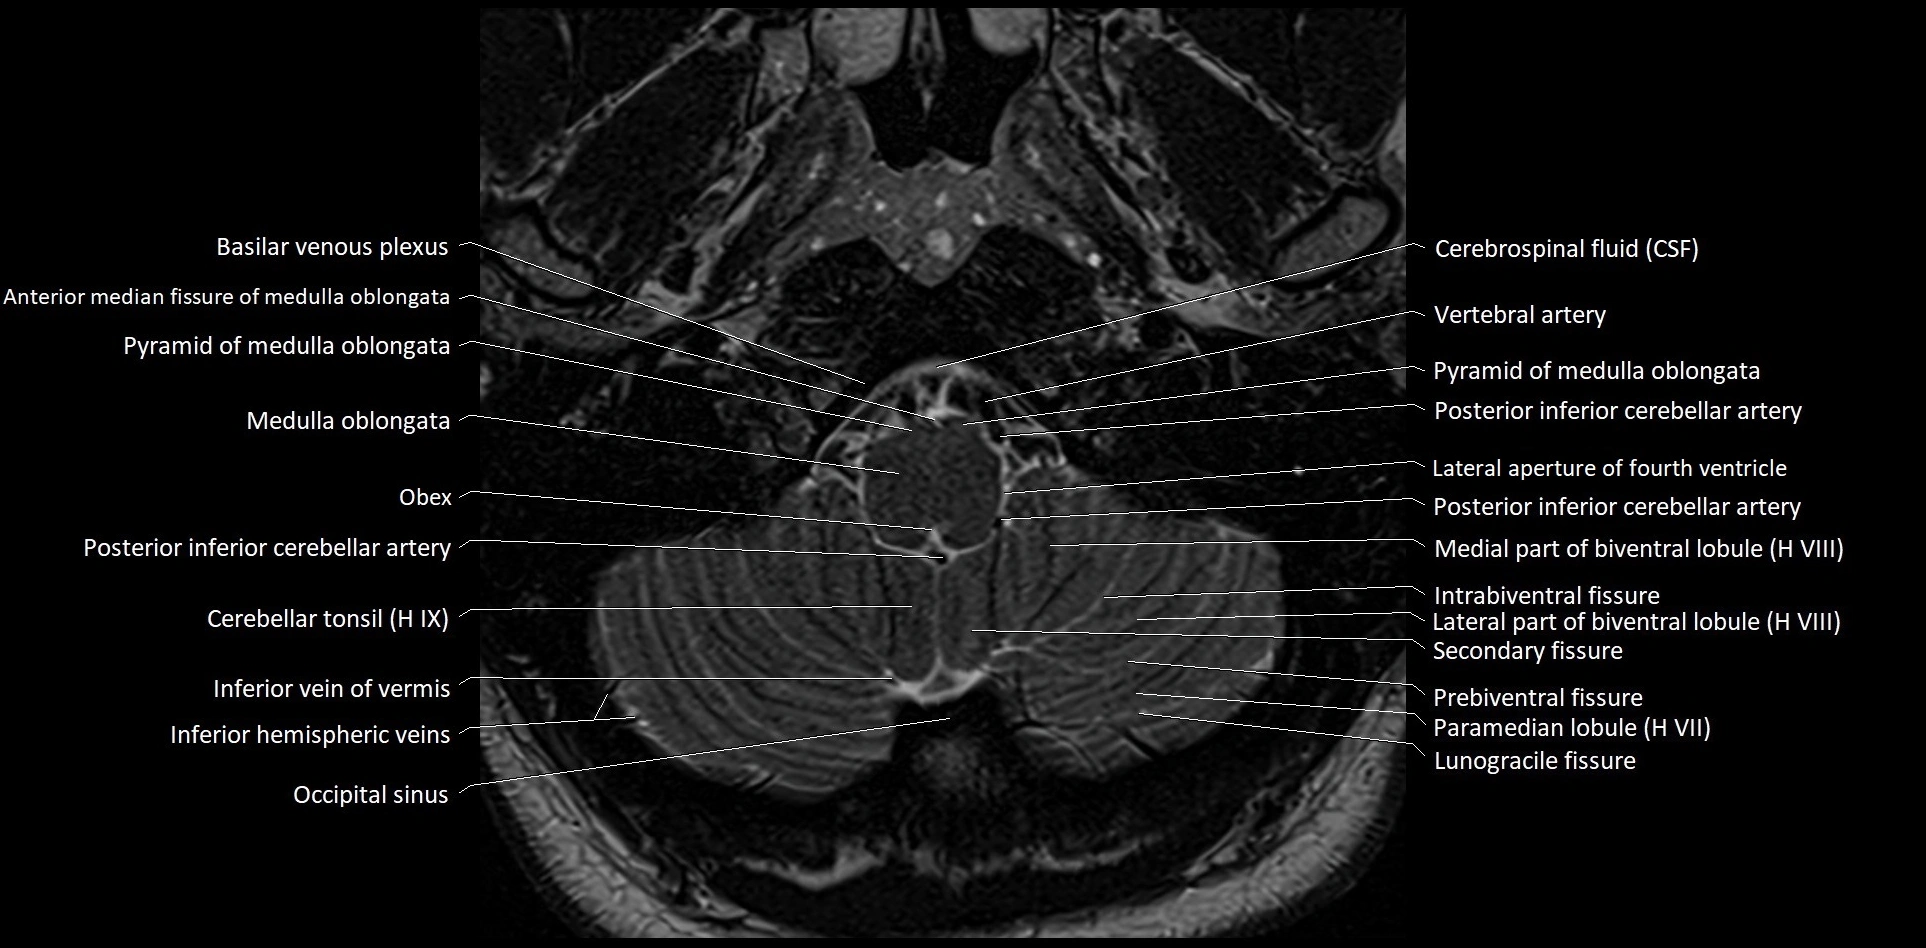

- Cerebellar tonsil (H IX)

- Inferior hemispheric veins of the cerebellum

- Inferior vein of vermis

- Intrabiventral Fissure of Biventral Lobule

- Lateral part of biventeral lobule

- Medial part of biventeral lobule

- Occipital sinus

- Paramedian lobule

- Paramedian lobule (HVII) of cerebellum

- Posterior inferior cerebellar artery

- Prebiventral fissure

- Secondary fissure